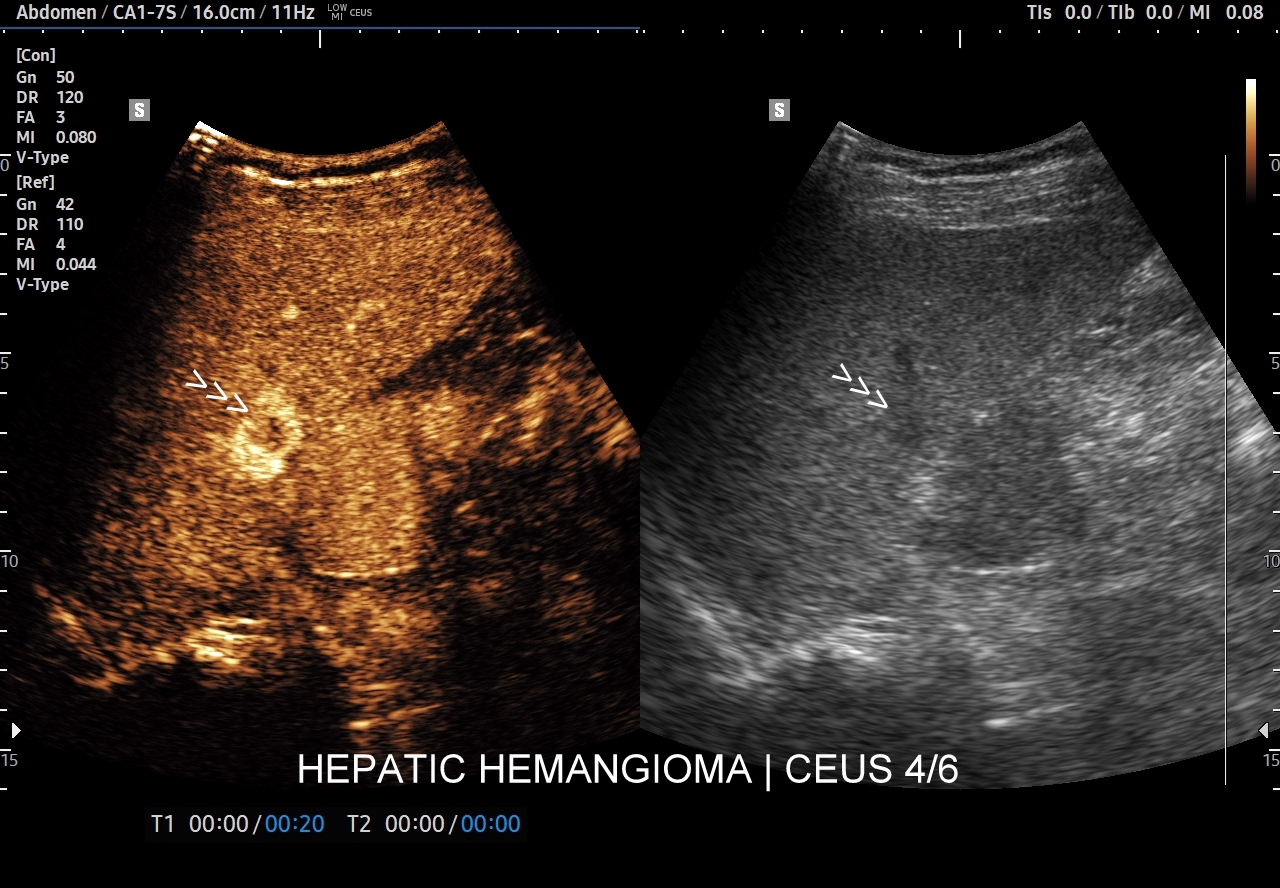

Najbardziej charakterystyczną cechą naczyniaka wątroby w badaniu CEUS jest jego wypełnianie w postaci guzkowej (ang. peripheral nodular enhancement) od obwodu ku centrum zmiany (ang. centripetal). Szybkość wypełniania bywa różnorodna, może być powolna lub szybka. W przypadku szybkiego wypełniania (tzw. flash-filling), w celu wykazania charakterystycznego centrypetalnego wypełniania niezbędna może być postprocessing’owa analiza poklatkowa zapisanego nagrania badania. W fazie późnej naczyniak wątroby pozostaje izowzmocniony lub hyperwzmocniony w stosunku do natywnego miąższu wątroby.

W przypadku dużych naczyniaków obszary, które uległy wykrzepianiu pozostają awaskularne przez wszystkie fazy badania CEUS, tj. nie wypełniają się kontrastem (nonenhancing). W przeciwieństwie do powyższego konstelacja, w której to w fazie wczesnej pojawia się wzmocnienie, a następnie w fazie wrotnej lub późnej ulega wypłukaniu (hypoenhancement) świadczy o cechach złośliwych diagnozowanej zmiany ogniskowej w wątrobie i wyklucza rozpoznanie naczyniaka.